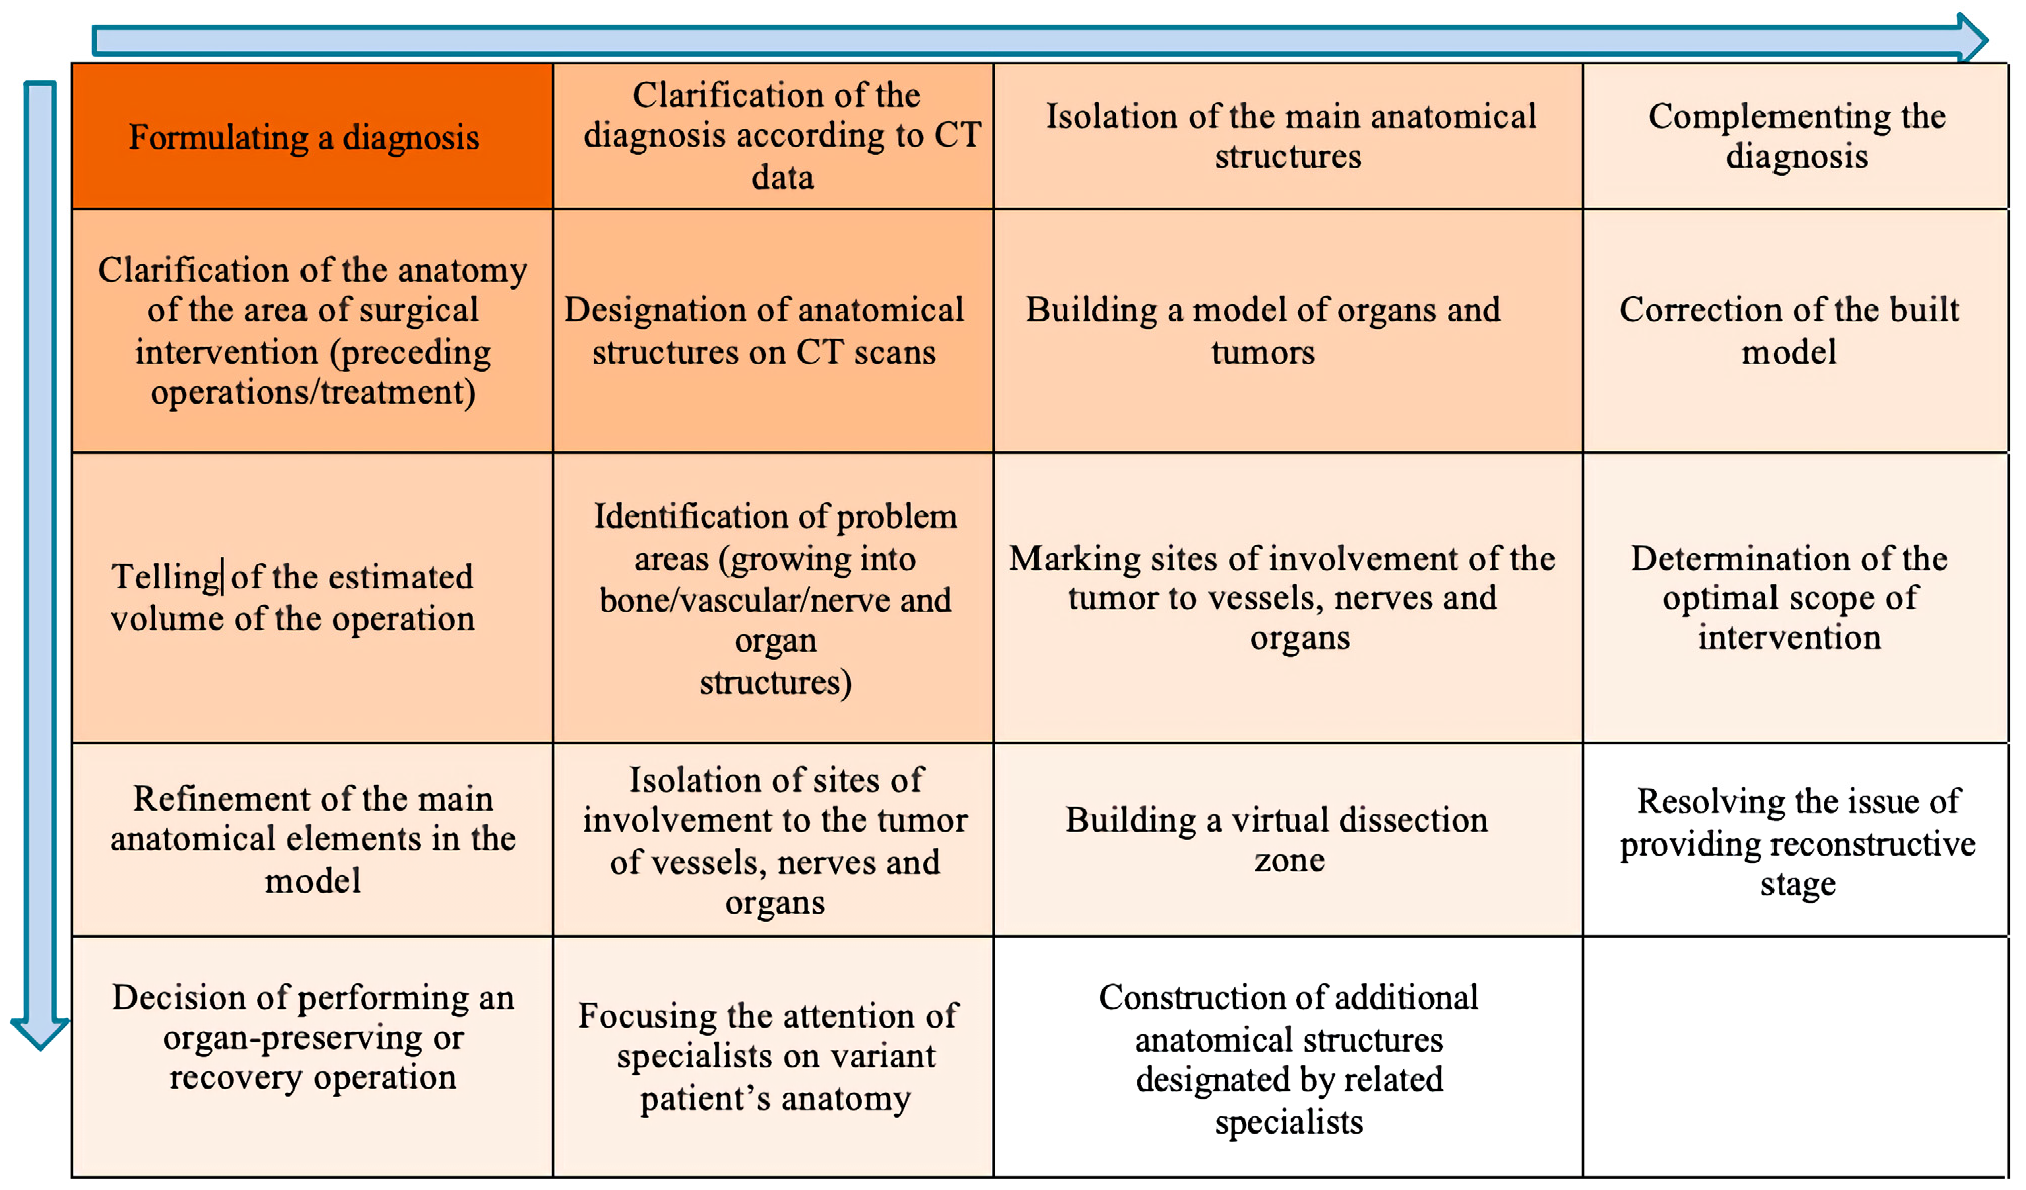

- Algorithm for creating a three-dimensional model of a surgical procedure by a multidisciplinary team.